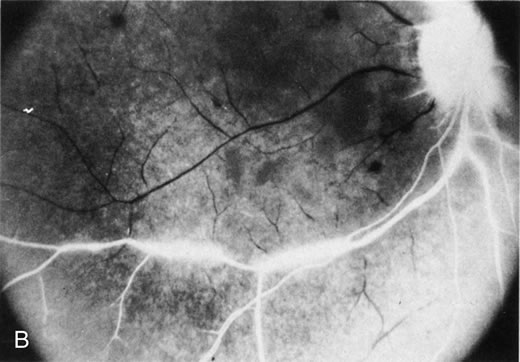

The finding of retinal vascular changes in patients with SLE correlates with the activity of the disease.214 The relationship of cotton-wool spots alone to CNS lupus has been debated, but to date no relationship has been established. Most experts feel that the finding of cotton-wool spots does not indicate the presence of CNS lupus. A much less frequent, severe retinal vasoocclusive disease has been described and does appear to be associated with CNS lupus, in particular, diffuse CNS dysfunction, such as an organic brain syndrome.214–223 This more severe retinal vasoocclusive disease may present as a central retinal artery occlusion, central retinal vein occlusion, branch artery occlusion, or most frequently, a diffuse retinal vasoocclusive process (Fig. 5), sometimes called retinal vasculitis. Although this last process sometimes has been called retinal vasculitis, the exact pathogenesis may not be true vasculitis. Cases of severe retinal vasoocclusive disease in SLE in association with the lupus anticoagulant also have been reported, and the retinal disease in these cases is presumed to be secondary to this autoantibody (Fig. 6).190,191 The prognosis for vision with this diffuse retinal vascular disease is poor and retinal neovascularization commonly develops. Panretinal photocoagulation may be of value in the treatment of the neovascularization of severe lupus retinopathy. Approximately 50% of eyes affected with this severe vaso-occlusive disease become blind. Although visual loss is common in those patients with severe retinal disease, in the more common mild retinopathy visual loss is unusual.223

Fig. 6. A. Fundus photograph and B. fluorescein angiogram demonstrating diffuse vaso-occlusive disease in a patient with systemic lupus erythematosus. This is peripheral nonperfusion of the retina. The patient had anticardiolipin antibodies. (Jabs DA, Fine SL, Hochberg MC, et al: Severe retinal vaso-occlusive disease in systemic lupus erythematosus. Arch Ophthalmol 104:558, 1986. Copyrighted 1986, American Medical Association. Reprinted with permission.)